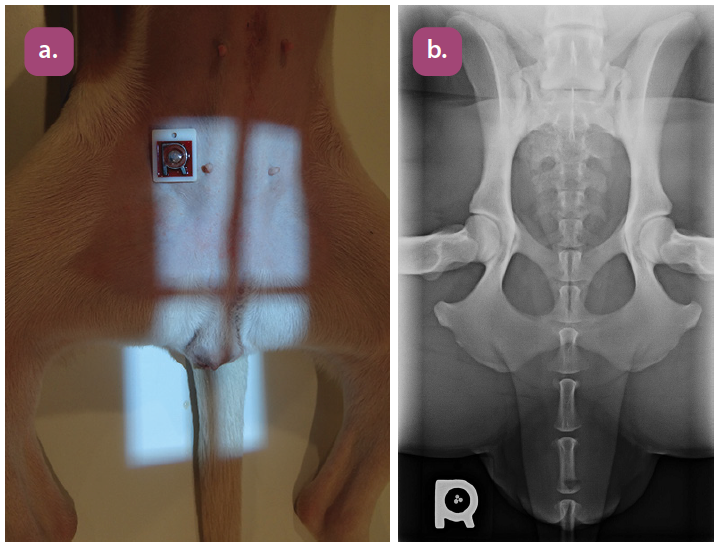

lateral projection of the pelvis

ventrodorsal extended hip projection

ventrodorsal frog leg projection